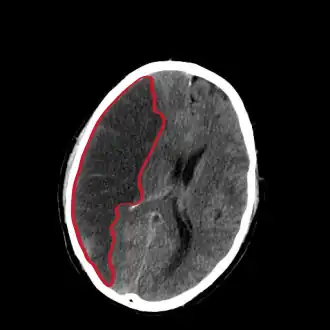

![]() Corte de una TAC del cerebro mostrando un infarto cerebral del hemisferio derecho (lado izquierdo de la imagen). | ||

La tomografía de cráneo revela zonas de infarto mayores de 1,6 cm, pero los cambios de la densidad no son inmediatos, por lo que es un estudio poco sensible. Además de la TC sin contraste, la inyección de contraste permite realizar una TC de perfusión y una angio-TC (angiotomografía). El 80 % de las enfermedades cerebrovasculares son debidas a un infarto cerebral isquémico y el otro 20 % a una hemorragia cerebral.[2] Un infarto debe distinguirse de una hemorragia cerebral y de una hemorragia subaracnoidea. Los infartos cerebrales varían en cuanto a gravedad, pues en un tercio de ellos se acaba produciendo la muerte del individuo.